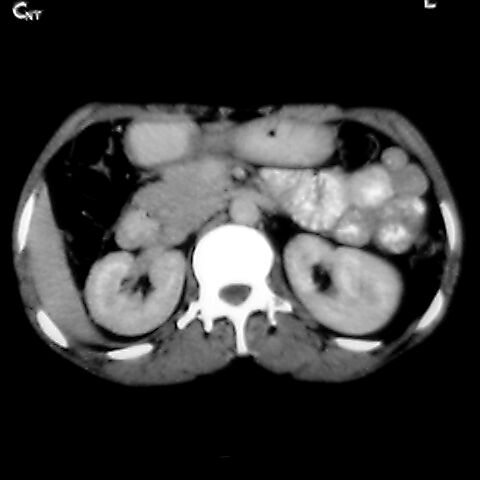

女 48岁 食道癌术前体检发现脾占位。

脾胀内部巨大低密度肿块,边界清或不清,中心坏死,轻度增强,内见散在钙化,结合食道癌病史多考虑:转移癌.

脾脏低密度灶伴钙化,增强化明显,中心见液化坏死灶,强化延时明显。考虑血管瘤。转移瘤待排。

考虑脾脏血管瘤,中央低密度为血栓形成